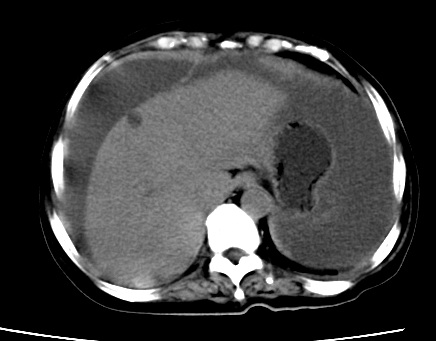

标题: CT23975:女61岁,腹部不适,明显消瘦

既往5年前卵巢癌行子宫及附件切除,右乳癌术后一年,考虑腹膜转移?

大量腹水,考虑腹膜转移。肝脏低密度灶。1囊肿,2转移。

1)结合病史,考虑腹膜及网膜转移瘤。2)肝脏多发性低密度灶,不排除转移瘤。3)大量腹水。

考虑卵巢癌行子宫术后复发,并肝、腹腔 、大网膜转移可能性大。

大量腹水。